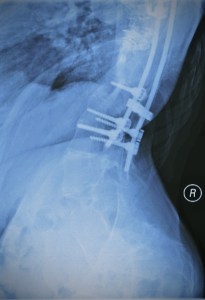

Spinal fusion is a procedure where bone grafts are used to fuse together the vertebrae in the spine so that it heals to form one long bone. Metal rods and screws are often implanted to assist the healing process… Yep, there are big f****** screws lodged in my spine. I’m gonna go lie down for a minute…

Ok I’m back. Sorry for the expletive. Thinking about this stuff written above makes me feel very peculiar. My body tenses up and I start to feel light headed. A deep seated feeling of despair emanates from my chest and I’m scared of what might happen if I let this despair take over. I become hyper aware of my spine and its lack of flexibility. I convince myself that I can feel the metal rods and screws in my spine and I want to rip out these things that have violated my body. But I can’t do that, for they saved my life. And as my therapist once said, I must learn to make friends with them.